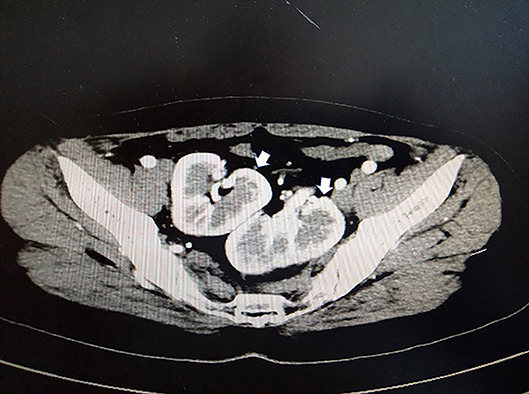

A 33-year-old female sought evaluation in our Department of General Surgery with a 2-year history of sporadic abdominal pain that had become aggravated during the past week. The character of pain became sharp and frequent. The pain was localized to the left lower abdomen. There was no nausea and vomiting. There was no history of abdominal trauma. The patient had a congenital anomaly of the kidneys and uterus; there was no menstruation. The patient had undergone an appendectomy in the past. On physical examination, the patient was afebrile. The abdominal examination revealed pain and a mass in the left lower quadrant area upon palpation. The mass was approximately 4 × 5 cm in diameters and was not circumscribed. The patient had no rebound tenderness and muscle rigidity. Laboratory testing revealed the following: white blood cell count, 7.13 × 109/L; neutrophilic granulocytes, 76.8%; hemoglobin, 120 g/L; and platelet count, 322 × 109/L. Computed tomography (CT) revealed an intestinal stromal tumor (Figure 1) and pelvic kidneys (Figure 2). Digestive tract radiography showed possible extraintestinal involvement (Figure 3). An intestinal stromal tumor was diagnosed and an abdominal laparotomy was performed; however, the intestinal tract was normal and a mass was noted in the sigmoid flexure. The tumor exhibited exophytic growth without infiltration and was 6.0 × 5.0 × 3.0 cm in size. The tumor and colon (proximal and distal length, 10 cm; ~25 cm) were excised. A rapid frozen section pathologic examination revealed a solitary fibrous tumor (SFT). A colon anastomosis was performed and the patient had fully recovered 7-days post-operatively. The final diagnosis was an ectopic ovary with corpora lutea bleeding (Figure 4). The patient recovered well after surgery and there were no post-operative complications. The patient was doing well at the 11-month follow-up visit. Written informed consent was obtained from the patient and The Third People's Hospital of Dalian had approved the study (NO. 2018-LW-001).

FIGURE 1

www.frontiersin.org

Figure 1. Contrast-enhanced computed tomography (CT) showing a cystic mass in the left lower quadrant (white arrow).